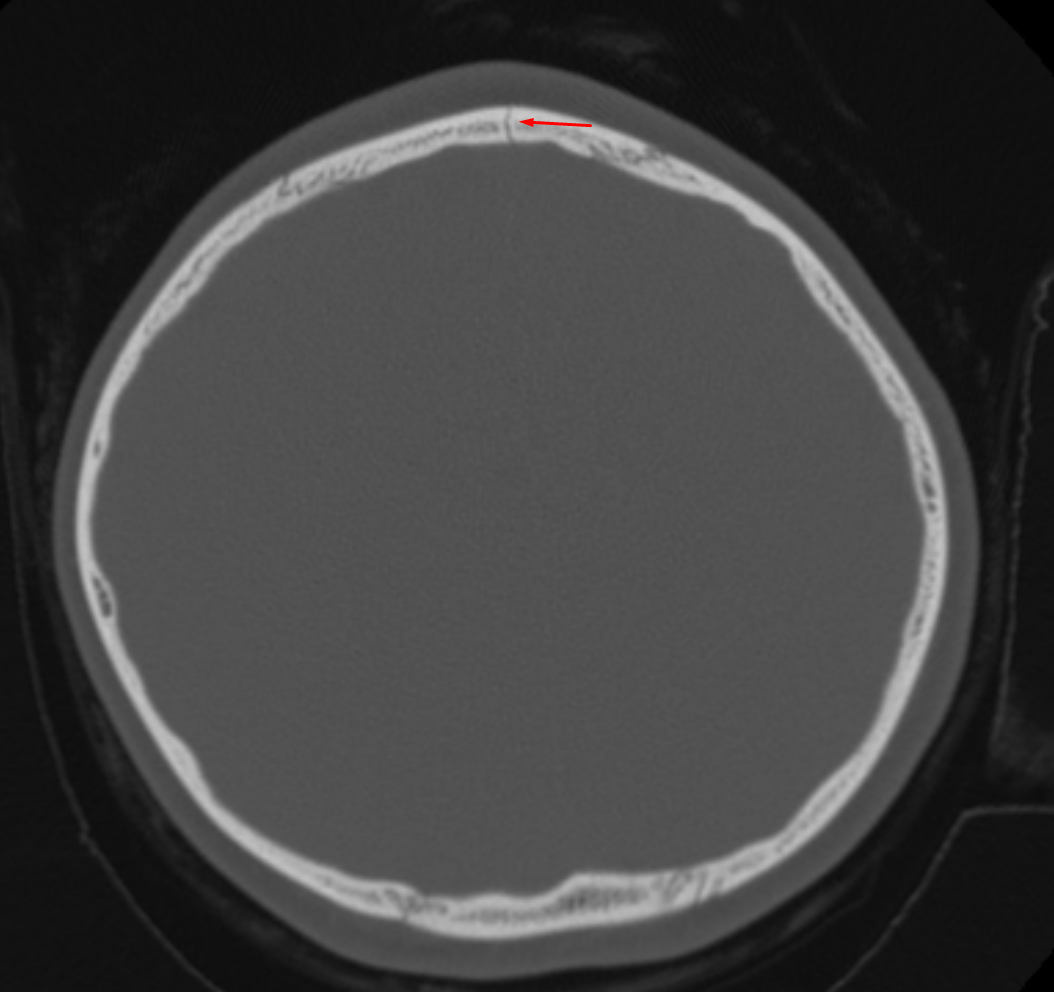

Age: 4

Sex: Female

Indication: MVC